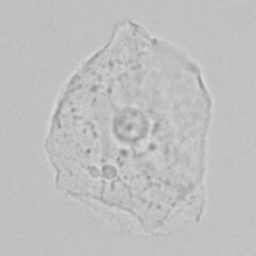

Squamous

In women, squamous epithelium is located at the base of the bladder and urethra, in men at the end of the urethra and foreskin. In addition, they line the inside of the vagina and perineum. Finding a small amount of squamous cells in urine is normal because these cells are constantly being renewed and replaced. Large amounts are usually caused by urine being collected after it has run down nearby areas such as the vagina, perineum or foreskin; this is referred to as contamination.

Sometimes these epithelial cells contain conspicuous dark granules; keratohyaline granules. These contain substances that contribute to the cornification of the skin layer. Their presence is normal and should not be confused with bacteria.